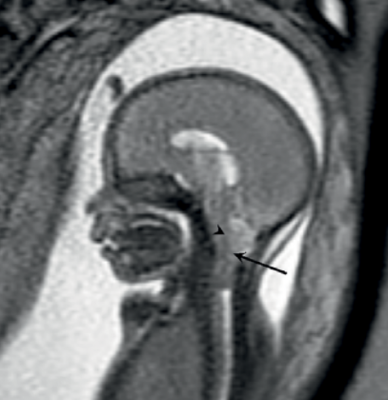

19. Imaging Zika Virus - Radiologic Assessment and Tracking in Prenatal Development